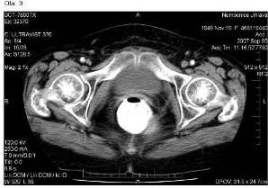

Pacientka zahájila chemoterapii režimem CDDP +

topotecan v květnu 2007. Po 4. cyklu v srpnu 2007 byla provedena

kontrolní CT vyšetření a bylo zjištěno úplné vymizení všech známek

nemoci jak v pánvi (obr. 3), tak na plicích (obr. 4).